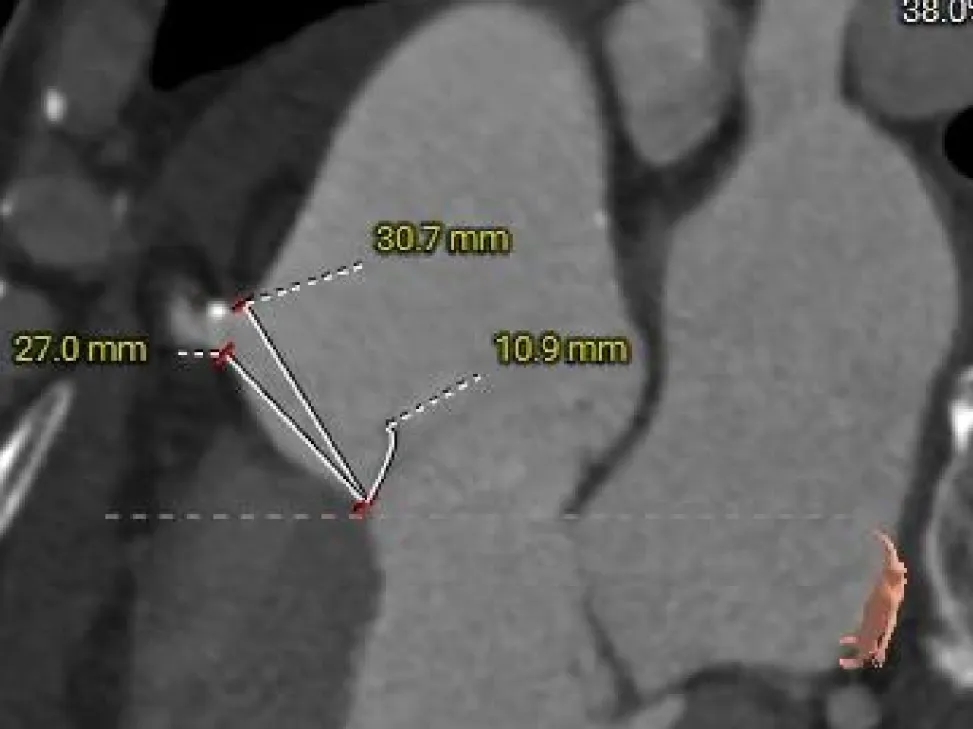

单纯反流三叶式主动脉瓣,瓣叶稍厚,右冠瓣脱垂;

瓣环径约为26.4mm,流出道偏直筒型;

瓣环水平夹角59°,横位心临界值,升主动脉明显扩张;